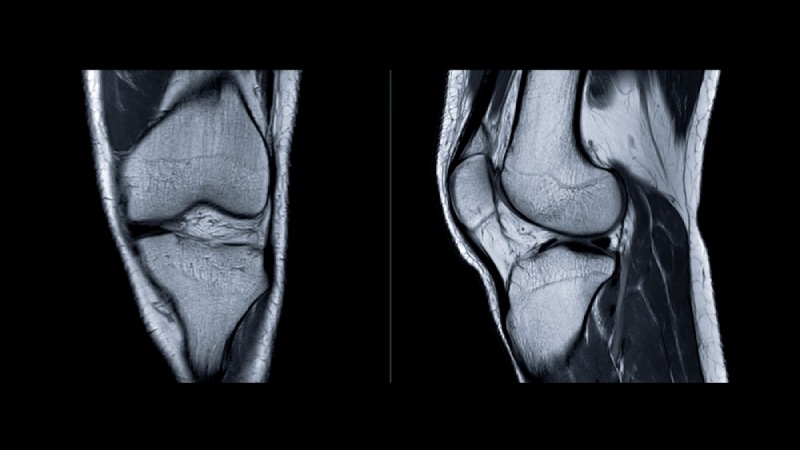

Để xác định nguyên nhân đau đầu gối khi vận động, bác sĩ sẽ xem xét các triệu chứng sưng, đau, nhạy cảm, ấm, bầm tím ở gối; đồng thời kiểm tra khả năng chuyển động của khớp. (4)

Tiếp đó, người bệnh có thể được chỉ định thực hiện xét nghiệm:

Đầu gối bị đau khi vận động lâu này nên được thăm khám sớm để kịp thời phát hiện bệnh lý tiềm ẩn, phòng ngừa biến chứng. Bạn nên ưu tiên những địa chỉ được trang bị máy móc hiện đại, chẳng hạn như Bệnh viện Đa khoa Tâm Anh. Đây là cơ sở ứng dụng hệ thống chụp CT 768 lát cắt Somatom Drive (Siemens – Đức), hệ thống cộng hưởng từ thế hệ mới MAGNETOM Amira BioMatrix (Siemens – Đức), hệ thống X-quang treo trần DigiRAD-FP (Hàn Quốc), máy đo loãng xương bằng tia X Horizon W (Hologic – Mỹ),… giúp hỗ trợ chẩn đoán bệnh chính xác và nhanh chóng.